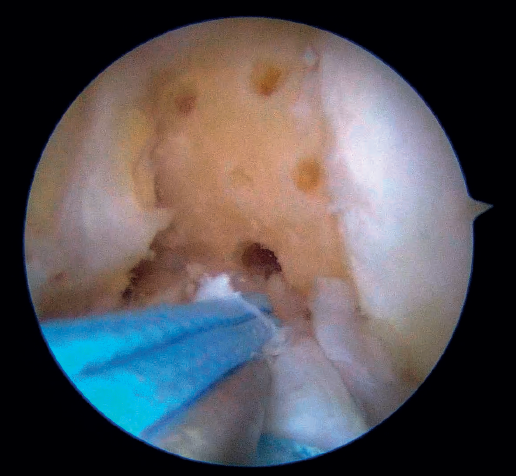

Outside the knee, the threads are loaded into a knotless anchor implant with a tape that will act as anterior reinforcement of the ACL when attached to the tibia. Once the implant has been loaded, it is inserted into the previously prepared site. This step is facilitated when viewing is made from the anteromedial portal, as it affords a better perspective of the zone (Figure 5). Once the implant has been inserted, the suture threads are cut at the level of the condylar wall.

With vision through the anterolateral portal, the tibial guide of the ACL is placed in the central zone of its distal insertion, and a tunnel is made with a 2.4 mm cannulated drill through which a loop-ended nitinol is passed and retrieved through the accessory anteromedial portal. The nitinol serves as a retriever, to load the tape through it and pass it through the tibial tunnel. Once the tape is retrieved, it is secured to the tibial cortex with a knotless anchor implant or button, tightening the tape with the knee in near full extension. If a threaded implant is used, it is important to check that no implant threads protrude at the cortex, as this could cause discomfort in the future.

Under arthroscopic vision, it is important to confirm tension of the ACL both in the full range of motion and with the use of a palpator and the Lachman and anterior drawer maneuvers (Figure 6).